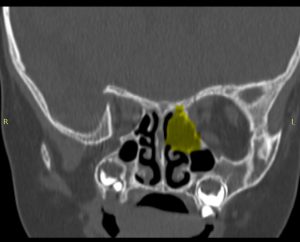

CT și RMN cranio‑faciale au evidențiat (Fig. 1):

- Formațiune tumorală etmoido‑orbitală stângă, cu extensie spre vârful orbitei;

- Distrucția prin compresie a peretelui medial orbital stâng, fără efracția periorbitei.

- Protruzia intraorbitară a formațiunii. Nu se pune in evidență extensie intracraniană

Figura 1: Secțiuni CT preoperatorii in plan axial si coronal, evidențiind tumora etmoido‑orbitală stângă.